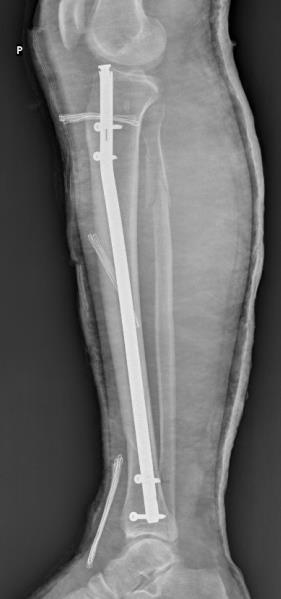

Silne bóle stawu kolanowego ograniczające ruchomość stawu w trzeciej dobie po zespoleniu złamania podudzia z obrazem Rtg jak poniżej są wskazaniem do: